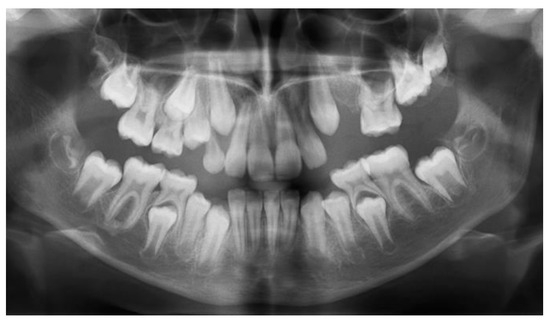

Clinical examination (Figure 1a) revealed no erupted teeth distal to the left upper canine, a left lateral open bite, and a slight shift of the upper midline to the left. Panoramic X-rays taken at this time showed delayed intraosseous development of the lateral left upper teeth as compared to the right side (Figure 1b) and no sign of mechanical obstruction. The agenesis of upper left premolars (24 and 25) was suspected but uncertain at the time.

Figure 1.

First visit; age of 4 y and 4 m. (a) Clinical aspect of the upper arch: no erupted teeth distal to the left upper primary canine; (b) panoramic X-ray.